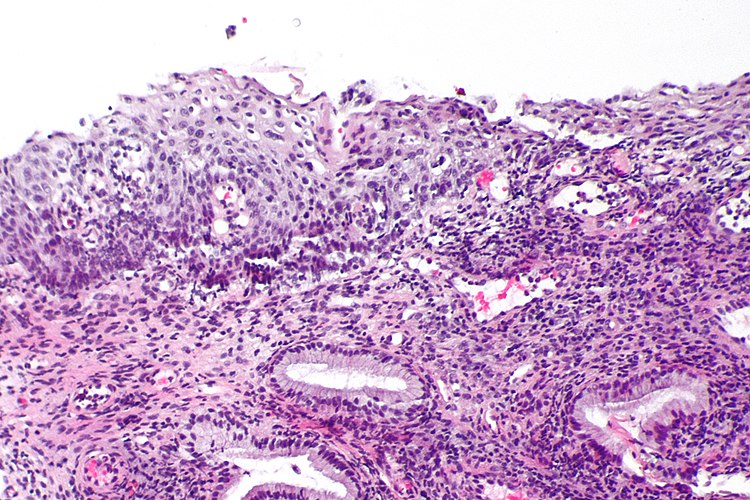

Histopathology

Diagnosis of HSIL on cytology requires specific criteria to be met. The cells are smaller with less cytoplasmic maturity than that of LSIL. Occasionally, the cytoplasm may be densely keratinized. HSIL cells occur singly as well as in sheets or syncytial aggregates. Though the size of the nucleus itself is variable, the cells must have a high nuclear-to-cytoplasmic ratio. The nuclei are often hyperchromatic but can be normo- to hyperchromatic. The chromatin can range from evenly distributed and fine to coarsely granular. Nuclear contours must be distinctly irregular with prominent indentations and/or grooves. Nucleoli are usually not a feature of HSIL, though may be seen when HSIL involves the endocervical glands.

Histologic criteria for HSIL exceeds the extent and degree of nuclear atypia allowed for a diagnosis of LSIL and includes less maturation, a higher nuclear-to-cytoplasmic ratio, decreased organization from the lower immature cell layers to the superficial mature layers (loss of polarity), a greater degree of nuclear pleomorphism, highly irregular nuclear contours, increased mitotic index and abnormal mitotic figures, especially within more superficial layers of the epithelium.

CIN3 must have full thickness atypia. When faced with not-so-straight-forward biopsies where the pathologist is debating between benign mimics of HSIL, such as immature metaplasia or atypical atrophy, utilizing the biomarker p16 may help distinguish them, as p16 shows intense and continuous staining in HSILs and suggests infection with a high-risk HPV type. [6][7]

Figure

Squamous intraepithelial lesion, high grade (HSIL). Increased nuclear/cytoplasmic ratio with moderate to severe dysplastic features of the nuclear membrane. Pap stain 40x. Contributed by Fabiola Farci, MD